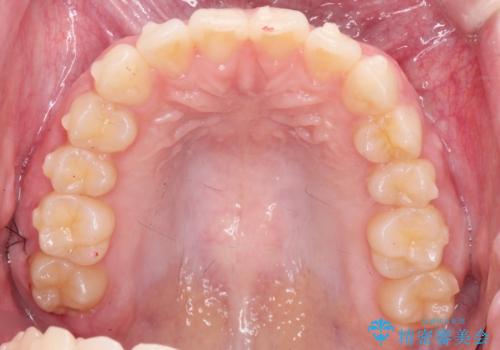

前歯のねじれをマウスピース矯正で治したい

- 前歯のねじれや がたつきを治したい、マウスピース矯正治療を希望され来院されました。

初診時程度のがたつきやねじれであれば、26枚以下のマウスピース矯正 モデレートプランで、比較的リーズナブルに矯正治療を受けていただくことができます。

実際の治療期間は約半年で仕上がりのような綺麗な歯並びを手に入れることができました。